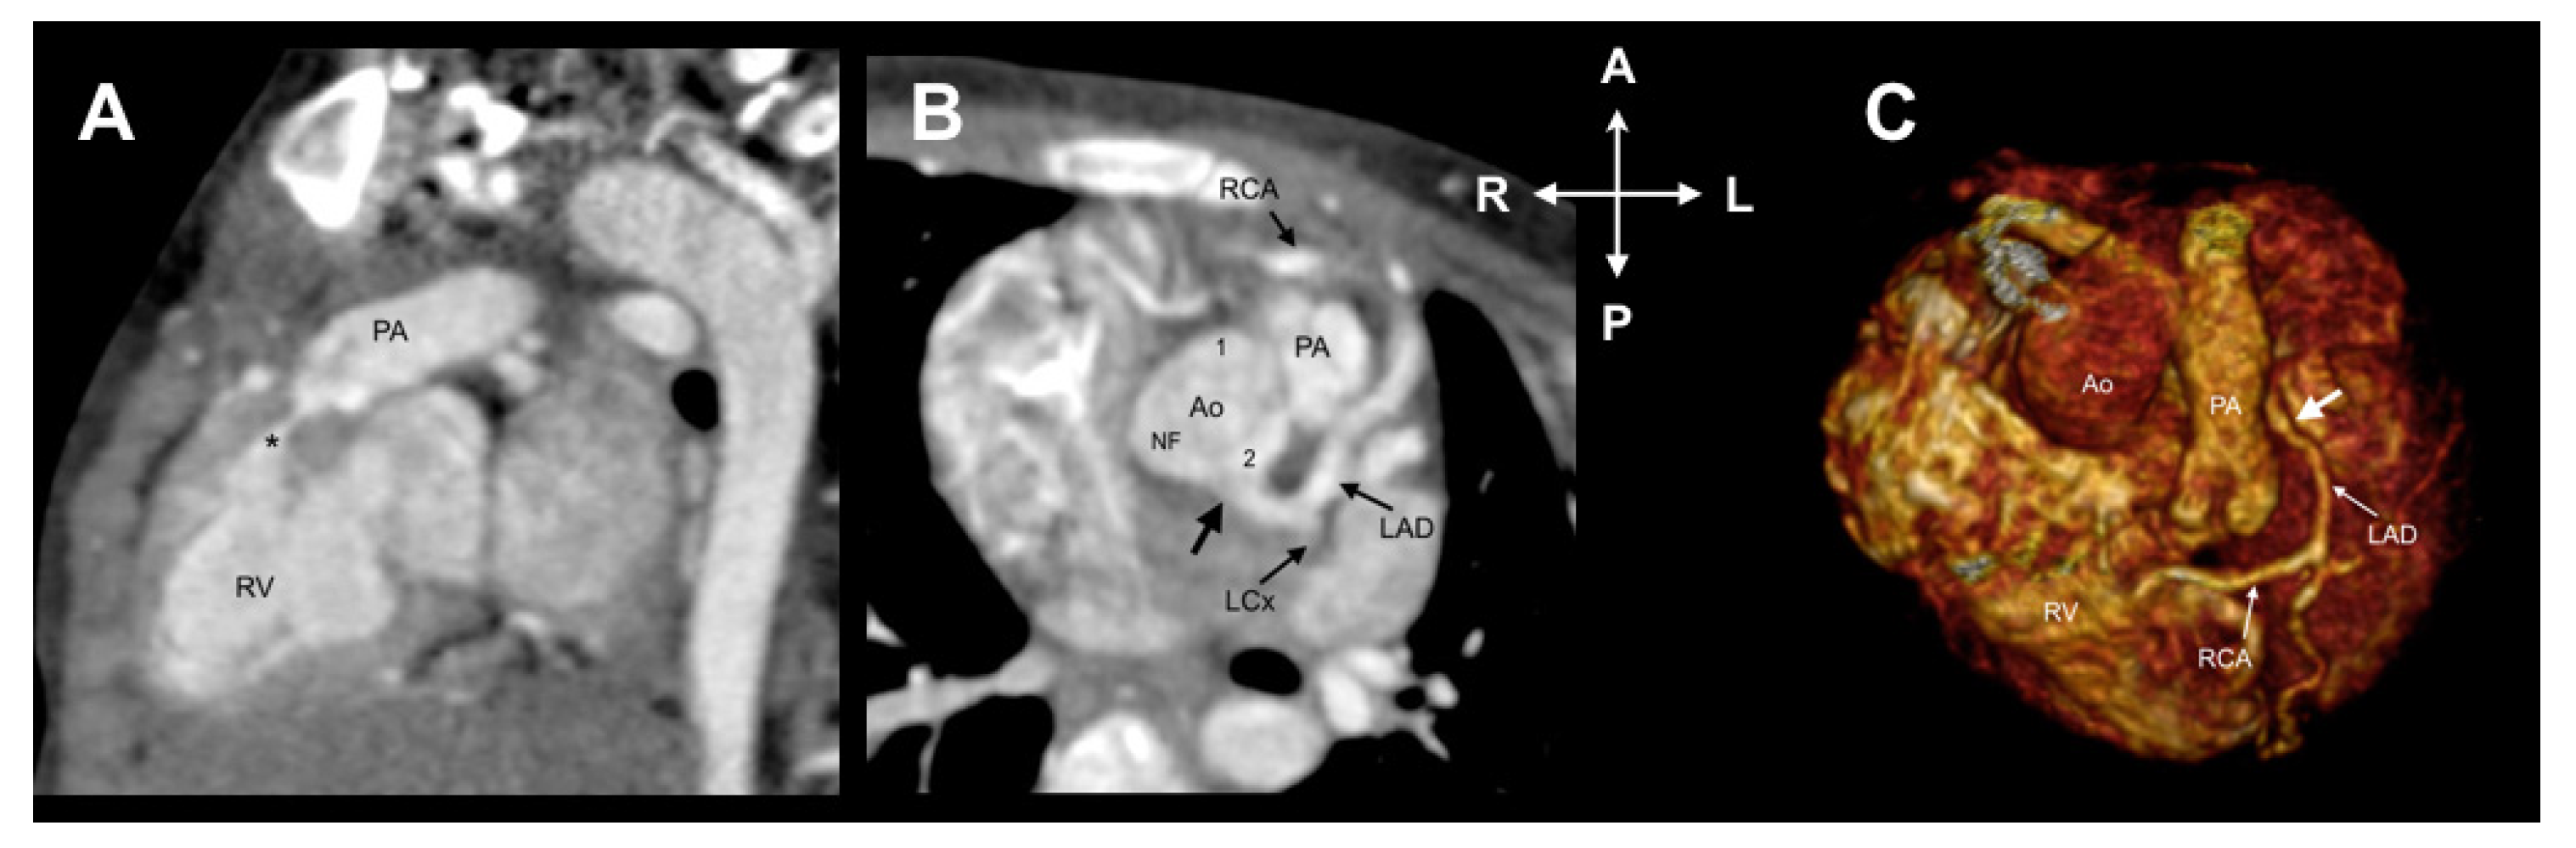

3.1. Lipton Classification

3.2. Leiden Convention Coronary Coding System